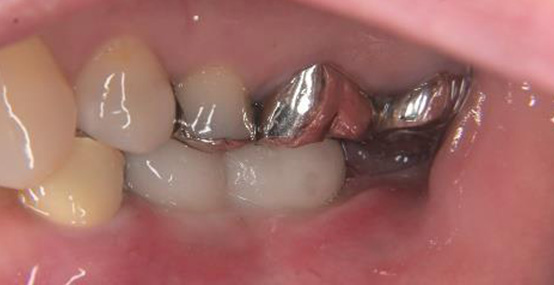

被せものの比較(左が術前、右が術後の写真です)

被せものの比較(上が術前、下が術後の写真です)

インプラントの植立位置を工夫することによって左下の被せものの厚みが確保され、被せものが割れにくい構造にすることができました。

術前の被せものの厚みが薄いという問題点も骨の高さ及びインプラント体を入れる深さを調整することにより十分な被せものの厚みが確保できています。